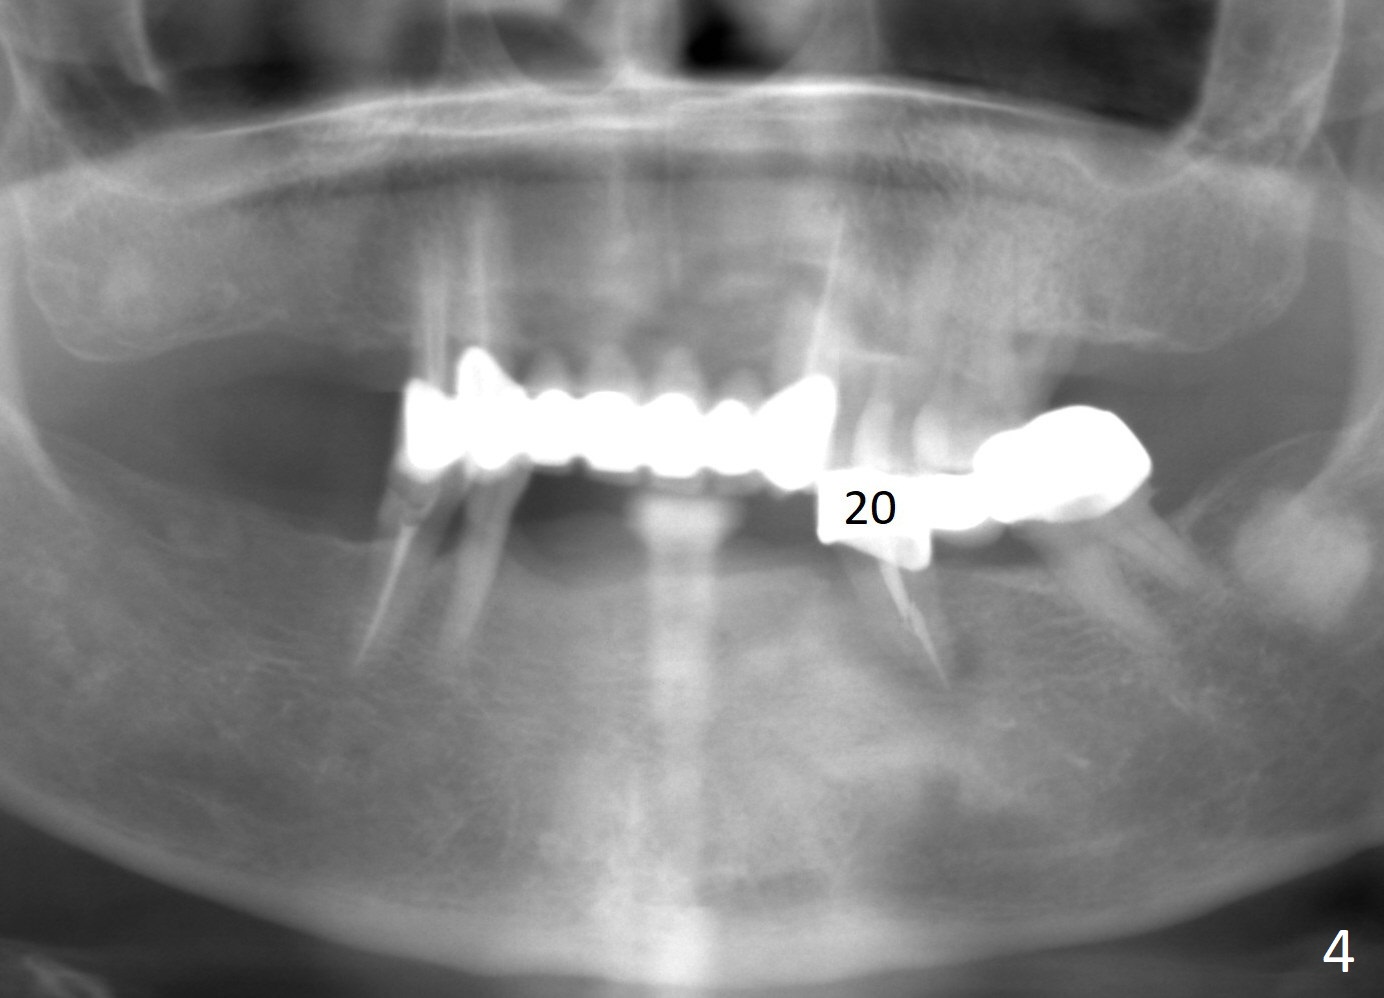

A 65-year-old woman used to have a long bridge (Fig.1). First, the portion mesial to #20 was sectioned. But the remaining portion kept chipping. RCT was retreated for the tooth #20 as the first step to have separate crowns at #18 and 20 and have a lower partial redo. Instead a new FPD was done between #18 and 20 in her own country (Fig.2). Two years later, the tooth #20 became symptomatic with increased pdl mesially (Fig.3*). Periradicular radiolucency increases in another 2 years (Fig.4). The apex of the affected tooth (yellow dashed line) is close to the Mental Loop (red dashed line, Fig.1-3). Although the loop is buccal to the apex of the 2nd premolar, an implant will not extend past the apex to avoid neuropathy (Fig.5). No Inferior Alveolar Nerve block will be administered. PA will be taken after pilot drill. The FPD will be sectioned between #18 and 19. To compensate for the short length of the implant, try to place a large one as long as the buccolingual bone allows. Adapt the lower RPD to the immediate provisional, which should be as small as possible, since the retention must be not too high.